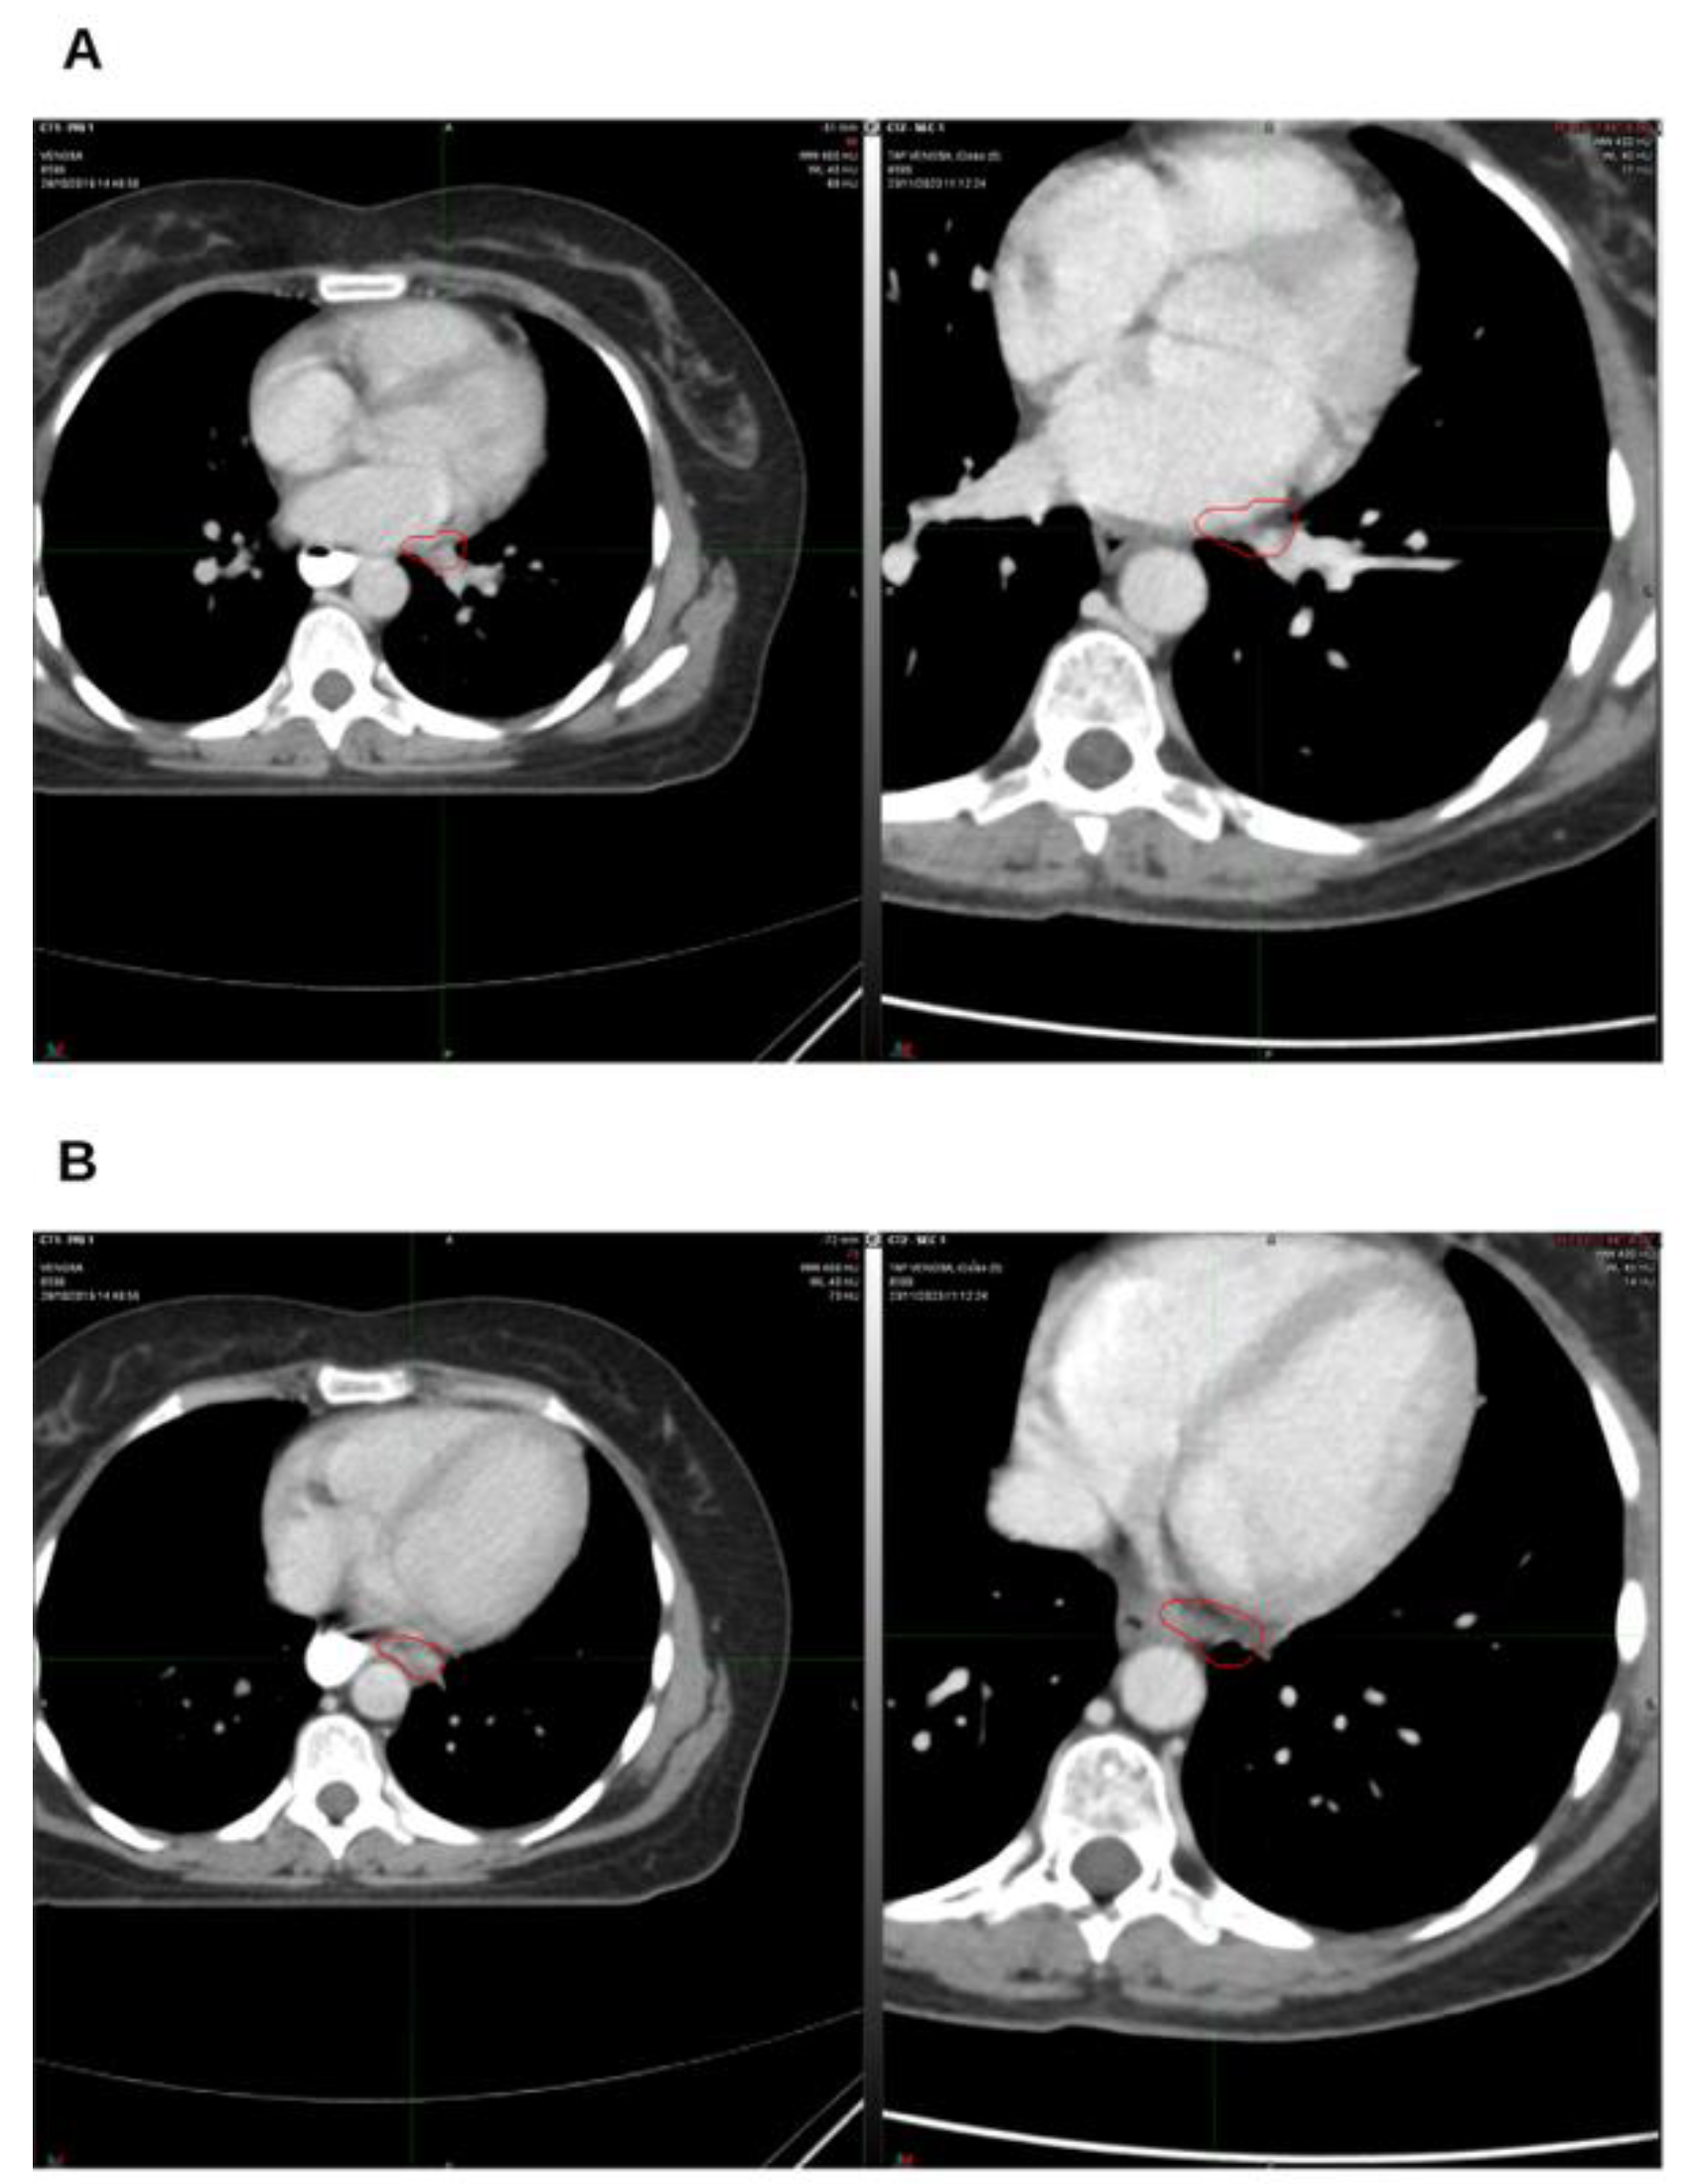

Background and Clinical Significance: Breast cancer is the most frequent malignancy in women. Advanced metastatic breast cancer is considered a treatable but incurable condition, with a median overall survival of only 2-3 years. Among its subtypes, triple-negative breast cancer (TNBC) accounts for a high proportion of breast cancer–related deaths. It is characterized by an aggressive clinical course, early recurrence, and a strong propensity for visceral and brain metastases. Case Presentation :We report the case of a Caucasian woman who, two years after being initially diagnosed and treated for TNBC, developed disease relapse with lung and mediastinal lymph node metastases. The patient received three months of chemotherapy combined with an adjuvant integrative protocol consisting of melatonin, cannabidiol, and oxygen–ozone therapy. This combined approach led to the complete disappearance of the lung nodules. Subsequently, stereotactic radiotherapy was performed and, in association with the ongoing integrative treatment, resulted in a significant reduction of mediastinal adenopathy. Introduction of immunotherapy, supported continuously by the same adjuvant strategy, achieved a complete and durable remission. Strikingly, the patient remained disease-free five years after the diagnosis of lung and mediastinal metastases. Conclusions: This clinical case highlights the potential benefit of using melatonin, cannabidiol, and oxygen–ozone therapy as part of an integrative approach in patients with aggressive metastatic TNBC. While it is not possible to establish causality from a single case, the sustained remission observed suggests that such unconventional adjuvant strategies could play a supportive role in enhancing the efficacy of standard oncologic therapies.